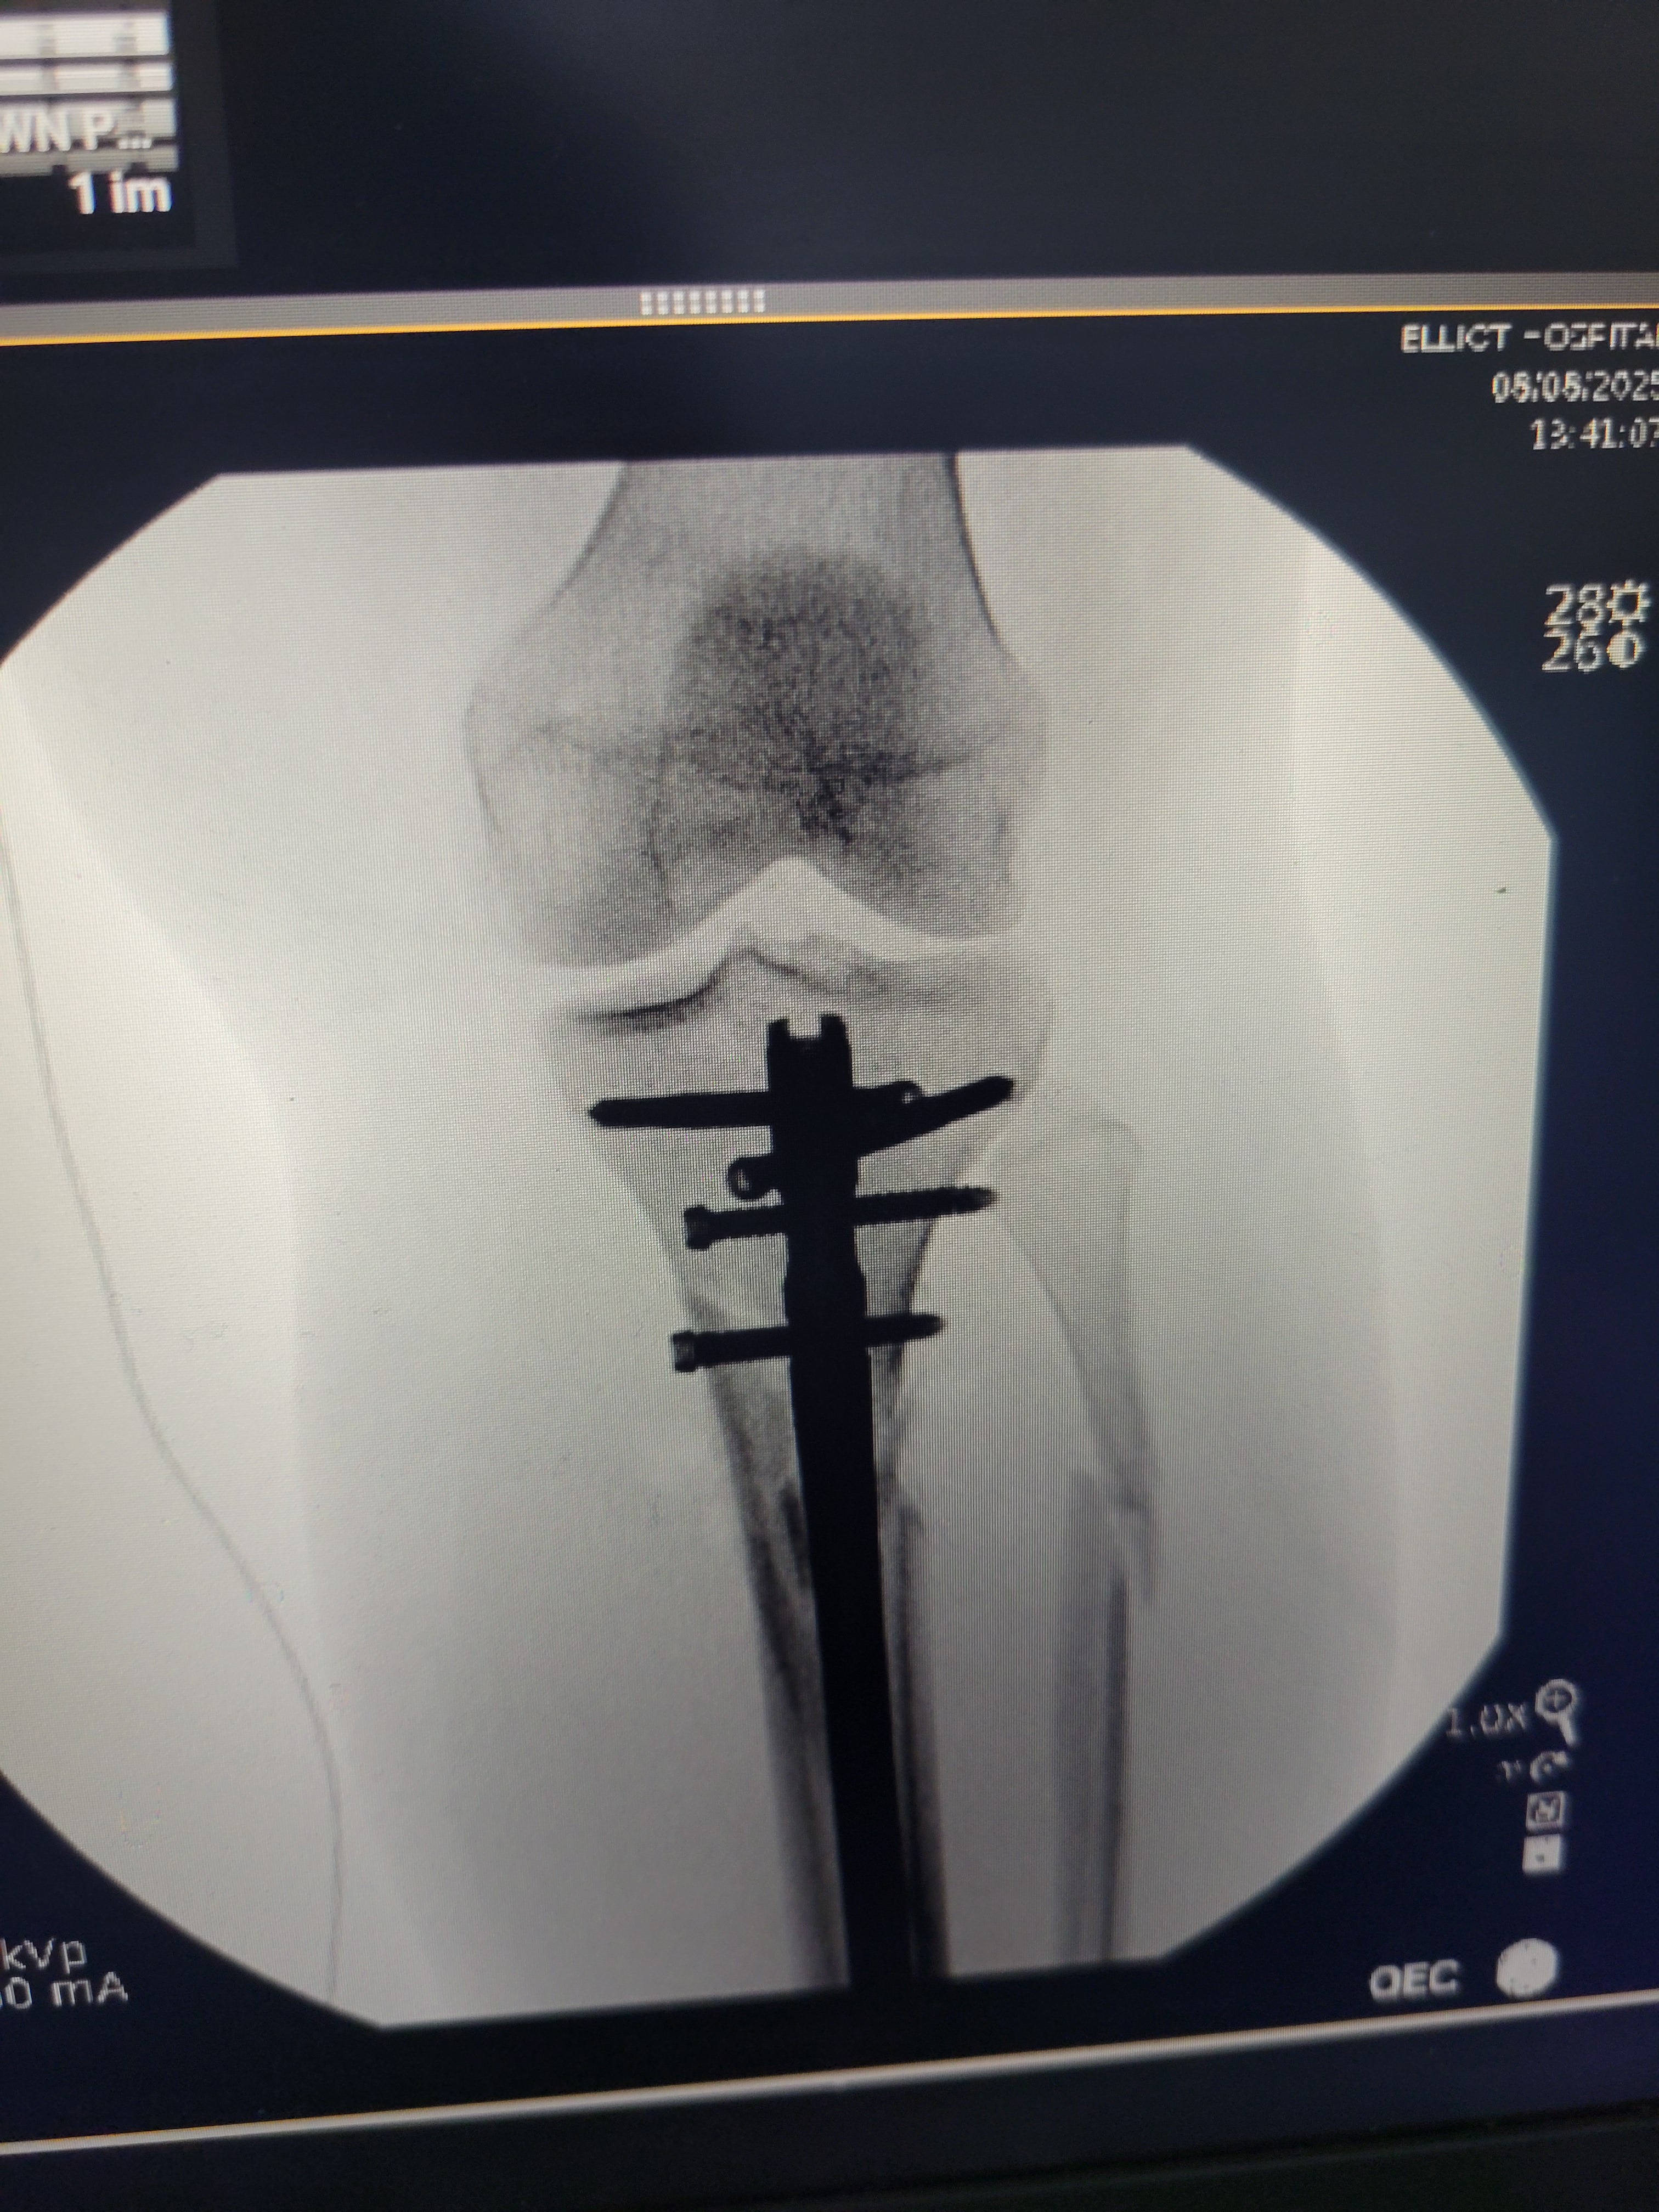

She suffered multiple broken bones in her left leg, a deep laceration in her right calf, torn muscles, broken ribs, severe concussion syndrome, and whiplash. She had to undergo surgery to insert a titanium rod and continues to deal with complications and unbearable pain every day.